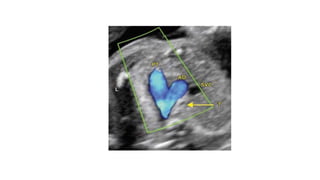

• #14 Figs A to C: Determination of the fetal right and left side by use of method described by Cordes et al. (A) The fetal head is aligned to the right of the screen The transducer is then rotated clockwise by 90° to obtain an image in the transverse plane at the level of the abdomen; (B) The spine is identified (yellow arrow), going clockwise from the spine is the right side followed by the left; (C) Showing diagrammatic representation that demonstrates the right and left sidedness according to the position of the spine in the transverse plane.